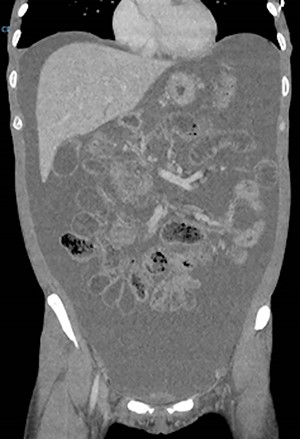

On examination, she had tense ascites but no clinical signs of peritonism. Initial blood tests demonstrated normal inflammatory markers, liver function and electrolytes. A computed tomography (CT) scan of the abdomen demonstrated gross ascites, but no defined pathology, including no mass lesions, portal vein thrombosis or peritoneal changes (Fig. 1). An ascitic drain was inserted and drained 4.6 litres of clear fluid. This was sent for cytology, biochemistry and culture (including for tuberculosis), with the results indicated in Table 1. Tumour markers (CEA, CA125, CA19-9 and AFP) were all within normal limits.